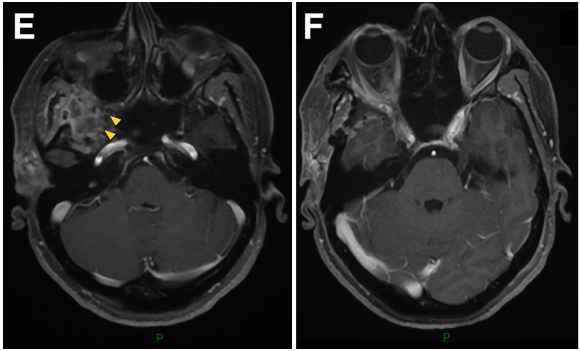

41岁男性,蝶眶脑膜瘤继发眼球突出,并延伸至前床突和蝶窦(SphS)。

图1A-D:术前MR显示蝶眶区脑膜瘤占位,增强病灶,浸润延伸至蝶腭窝(黄色箭头)。

术中操作:Froelich教授经翼点入路开颅,剥离海绵窦侧壁后,行硬膜外前床突切除术。切除硬脑膜内肿瘤及侵袭硬脑膜及眶周的肿瘤。使用颅包膜补片对硬脑膜缺损进行水密封闭后,剥去圆孔(FR),暴露翼腭窝(PPF)。肿瘤沿V2神经鞘播散生长,磨除上颌窦(MaxS)后,打开蝶窦(SphS)。

术后组织病理学:I级脑膜上皮型脑膜瘤。

术后临床情况:眼球突出症状立即好转,术后恢复好,病程平稳。术后V2神经功能包括角膜感觉正常,无干眼、流泪异常等症状,按期拆线出院。

▼术后影像复查:证实肿瘤被完全切除。E-H:术后轴位MR图像显示肿瘤完全切除。